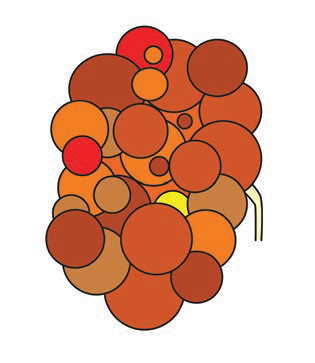

Figura 2.9.5.3. Poliquistosis renal autosómica dominante (2 imágenes)